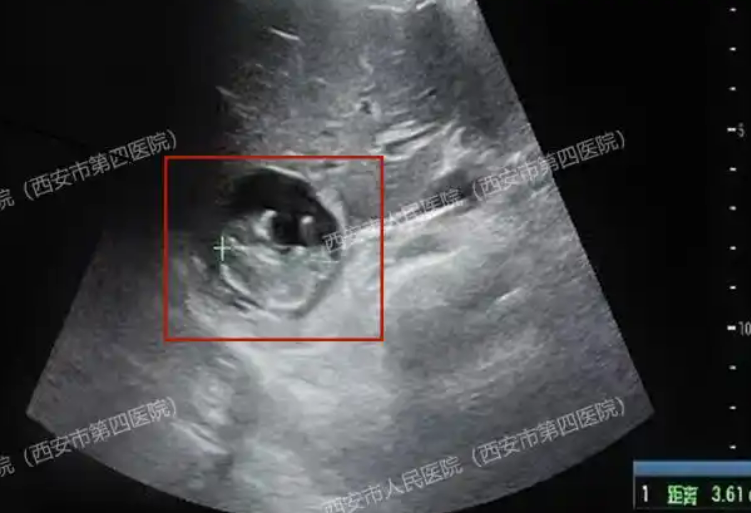

那张显示怀孕的验血单握在手中,B超探头却在子宫内反复搜寻无果。谁也没想到,一个近11周的孕囊,正寄生在人体血供最丰富的器官上。

然而,接下来的B超检查却让医生皱起了眉头:子宫和输卵管内空空如也,那个本应在此安家的孕囊,神秘“消失”了。

就在王女士几乎要相信这是一场“生化妊娠”的乌龙时,更精细的检查揭开了真相:这个重约1.5公斤、拥有双重血供(门静脉和肝动脉)的人体“超级工程”——肝脏,成了胚胎的落脚点。

这不是科幻情节,而是近日发生在西安的真实病例:原发性肝脏妊娠。一种发病率约为1/1000万至1/1.5亿、全球不超过50例的极端异位妊娠。